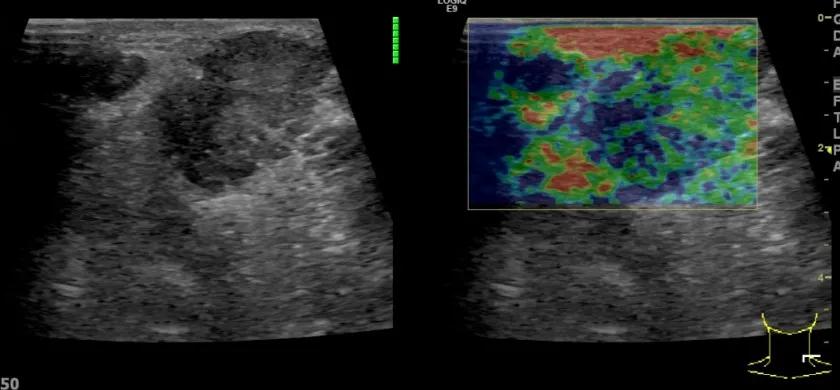

第三例是甲状腺癌患者,双侧甲状腺癌切除术后、碘治疗后一年余效果欠佳,超声显示左颈3区3枚低回声结节,穿刺示甲状腺乳头状癌转移。患者不愿意手术,希望采取局部治疗。对病灶进行液体隔离后采取热消融术,由于淋巴结较小,热消融一分钟左右完全灭活,术后增强影像显示没有脏器充填。

(病例3图例)